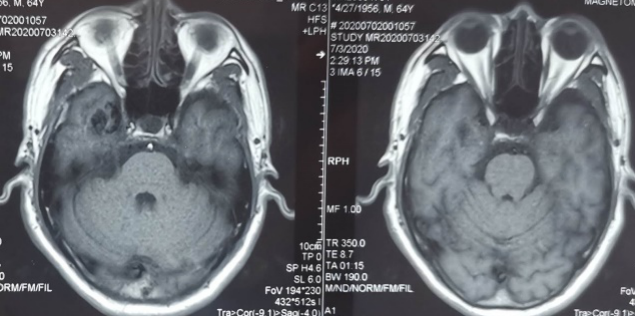

外院头颅CT示右侧颞叶钙化灶,头颅MRI示见右侧颞叶流空信号,考虑动静脉畸形。